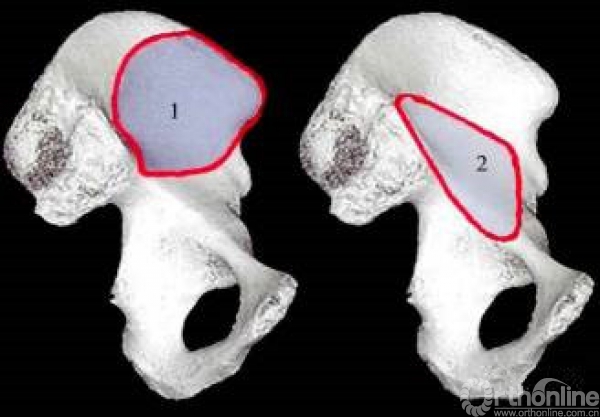

五个手术窗口

窗口1:髂嵴和髂腰肌之间,将肌肉向内侧牵拉。暴露髂骨。

窗口2:髂腰肌和髂外血管之间。将髂外血管向内侧牵拉,髂腰肌向外侧牵拉,暴露骶髂关节,耻骨支。